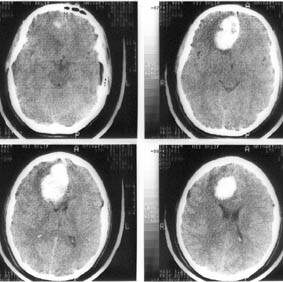

Инсу́льт (лат. insultus «наскок, нападение, удар»), устар. апопле́кси́я (др.-греч. ἀποπληξία«паралич») — острое нарушение кровоснабжения головного мозга (острое нарушение мозгового кровообращения, ОНМК), характеризующееся внезапным (в течение нескольких минут, часов) появлением очаговой и/или общемозговой неврологической симптоматики, которая сохраняется более 24 часов или приводит к смерти больного в более короткий промежуток времени вследствие цереброваскулярной патологии. источник wikipedia.org Эта болезнь совершенно безразлична к возрасту, ею подвержены как взрослые люди, так и молодежь. Но важно помнить, что своевременное лечение спасет человеку жизнь. Ваш организм предупредит вас о имеющихся проблемах, которые ведут к инсульту, примерно за месяц. Не прозевайте эти симптомы! 1. Высокое давление Высокое давление это всегда плохо. Этот симптом наносит сильный удар по нервным окончаниям и сосудам. Но что более страшнее - формирование тромбов в кровотоке. Если эти тромбы доберутс

Инсу́льт (лат. insultus «наскок, нападение, удар»), устар. апопле́кси́я (др.-греч. ἀποπληξία«паралич») — острое нарушение кровоснабжения головного мозга (острое нарушение мозгового кровообращения, ОНМК), характеризующееся внезапным (в течение нескольких минут, часов) появлением очаговой и/или общемозговой неврологической симптоматики, которая сохраняется более 24 часов или приводит к смерти больного в более короткий промежуток времени вследствие цереброваскулярной патологии.

Эта болезнь совершенно безразлична к возрасту, ею подвержены как взрослые люди, так и молодежь. Но важно помнить, что своевременное лечение спасет человеку жизнь.